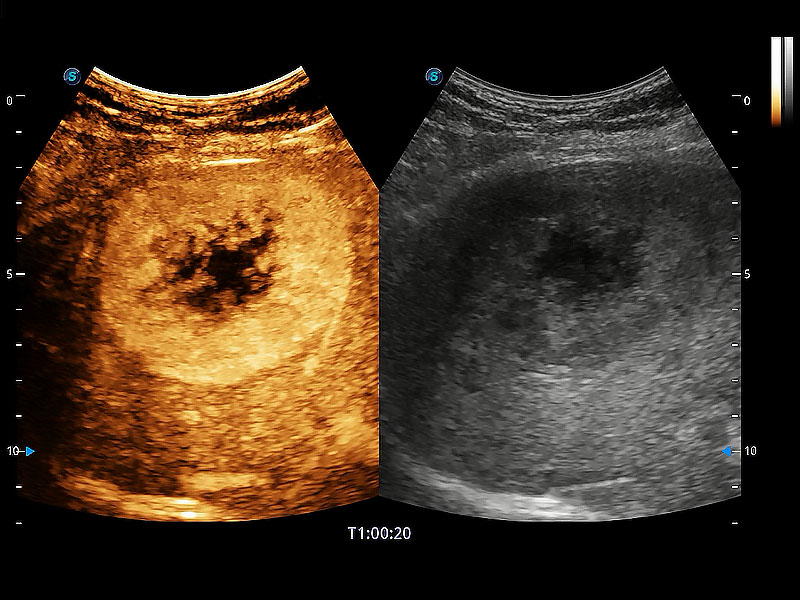

(犬)肝脏

(犬)肾脏显微血流

高性能和先进的临床应用工具可以为动物医生提供临床信心。ProPet 80 搭载了先进的腹部和浅表应用工具,帮助医生在日常临床实践中发挥前所未有的作用。

• Micro F 显微血流成像

极大提升超低速微细血流的检出能力,同时更精准地滤除软组织和超声信号,为兽用医生提供以往无法通过常规血流获得的疾病诊断信息。